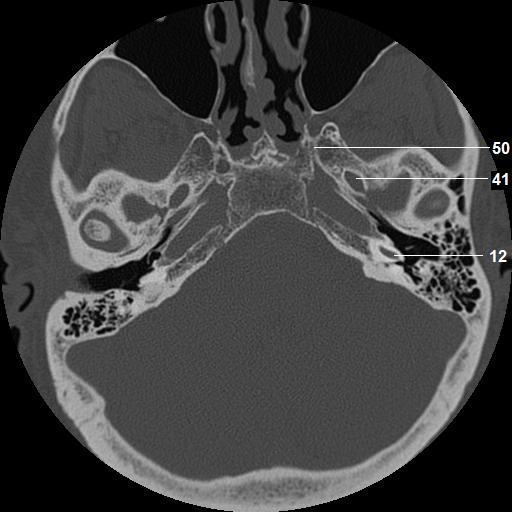

12. basal turn, cochlea

41. foramen ovale

50. vidian canal